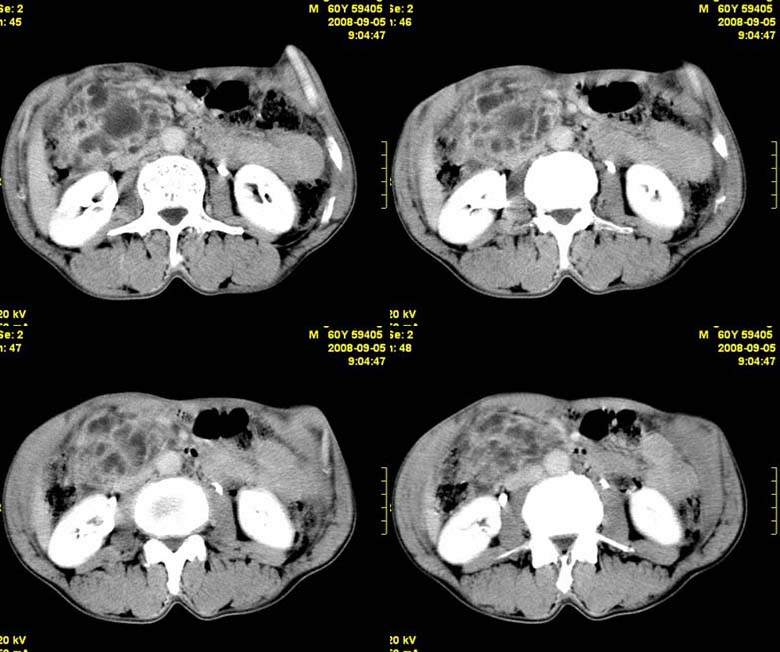

标题: CT15580:M60Y,胰腺病变,平扫+增强 [打印本页]

标题: CT15580:M60Y,胰腺病变,平扫+增强

患者,男, 60,既往有间歇腹痛病史多年,现右上腹痛,加重一月,伴右后背部疼痛,无黄疸,无发热。

考虑胰腺囊腺瘤或慢性胰腺炎

胰头区增大,胰管明显扩张,不均匀强化,且与 周围结构不清,后背疼痛,考虑为胰腺头部胰腺癌。

胰头囊腺癌

胰头囊腺癌

慢性胰腺炎

胰头囊腺癌

慢性胰腺炎并胰头癌

胰头囊腺癌。

胰腺囊腺瘤可能性大,囊腺癌不除外.

同意胰头部囊腺癌。

胰头囊腺癌可能性大。

考虑胰腺囊腺瘤或慢性胰腺炎

胰头囊腺癌

结合病史考虑慢性胰腺炎伴脓肿形成。

胰腺囊腺癌/慢性胰腺炎,建议查肿瘤标志物。

胰头囊腺瘤/囊腺癌.

胰腺炎,胰液滞留性假囊肿

考虑胰腺囊腺瘤或慢性胰腺炎。

胰头区增大,胰管明显扩张,不均匀强化,且与 周围结构不清,后背疼痛,考虑为胰腺头部胰腺癌。

胰头囊腺癌

考虑胰腺囊腺瘤或慢性胰腺炎可能性大

粘液性囊腺瘤

同意胰头部囊腺癌

胰头囊样增大不均匀强化,腺管扩张。结合病史首诊慢性胰腺炎、假性囊肿